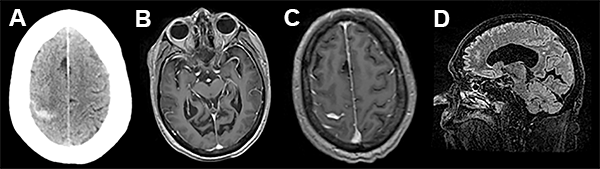

A las 72 hs de la segunda intervención comienza con cefaleas intensas, náuseas, trastorno del sensorio por lo cual se realiza nueva internación, evidenciando mediante TAC sangrado subaracnoideo (fig. 2).

En el presente trabajo, los autores reportan un evento hemorrágico cerebral como complicación de una fistula de líquido cefalorraquídeo (LCR) asociada a una cirugía espinal lumbar mini invasiva. Dicho evento se desencadenó 72 hs luego de la reparación de la fístula de LCR, presentándose como una hemorragia subaracnoidea de la convexidad cerebral. Esta complicación ha sido descrita por numerosos grupos,1-5 siendo la localización mas frecuente el cerebelo. Si bien las imágenes de tomografía y resonancia magnética nuclear evidencian la presencia de hemorragia subaracnoidea en el surco central derecho, llama la atención la asimetría de surcos con hipodensidad en el área premotora derecha, similar a los hallazgos asociados con una trombosis venosa. Más aún, considerando que el paciente tiene antecedentes de trombosis venosa profunda e ingresa a las 72 horas por trastornos del sensorio (difícilmente explicables sólo por una hemorragia subaracnoidea de la convexidad), no podemos descartar con las imágenes brindadas la presencia de trombosis venosa, complicación también descripta como consecuencia de una perdida de LCR.6-9 Si bien ambas complicaciones son de muy baja ocurrencia, es importante reconocer su existencia a la hora de evaluar un postoperatorio de cirugía espinal complicado con fistula de LCR en pacientes añosos.